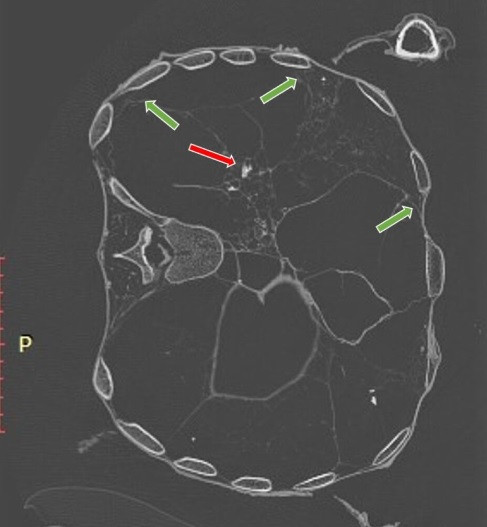

Phổi của người đàn ông có vết sẹo do từng mắc bệnh lao nặng nhưng không phải nguyên nhân tử vong. Nhóm nghiên cứu nhận định nguyên nhân dẫn tới cái chết của người này đến từ hành vi bạo lực.

Cụ thể, kết quả phân tích bằng 3D-CT chỉ ra người đàn ông trên tử vong do cú đánh chí mạng vào đầu và bị đâm vào lưng trong lúc đang đứng hoặc quỳ. Những vết thương nghiêm trọng này gây ra bởi một hoặc hai kẻ tấn công vào khoảng năm 996 - 1147.